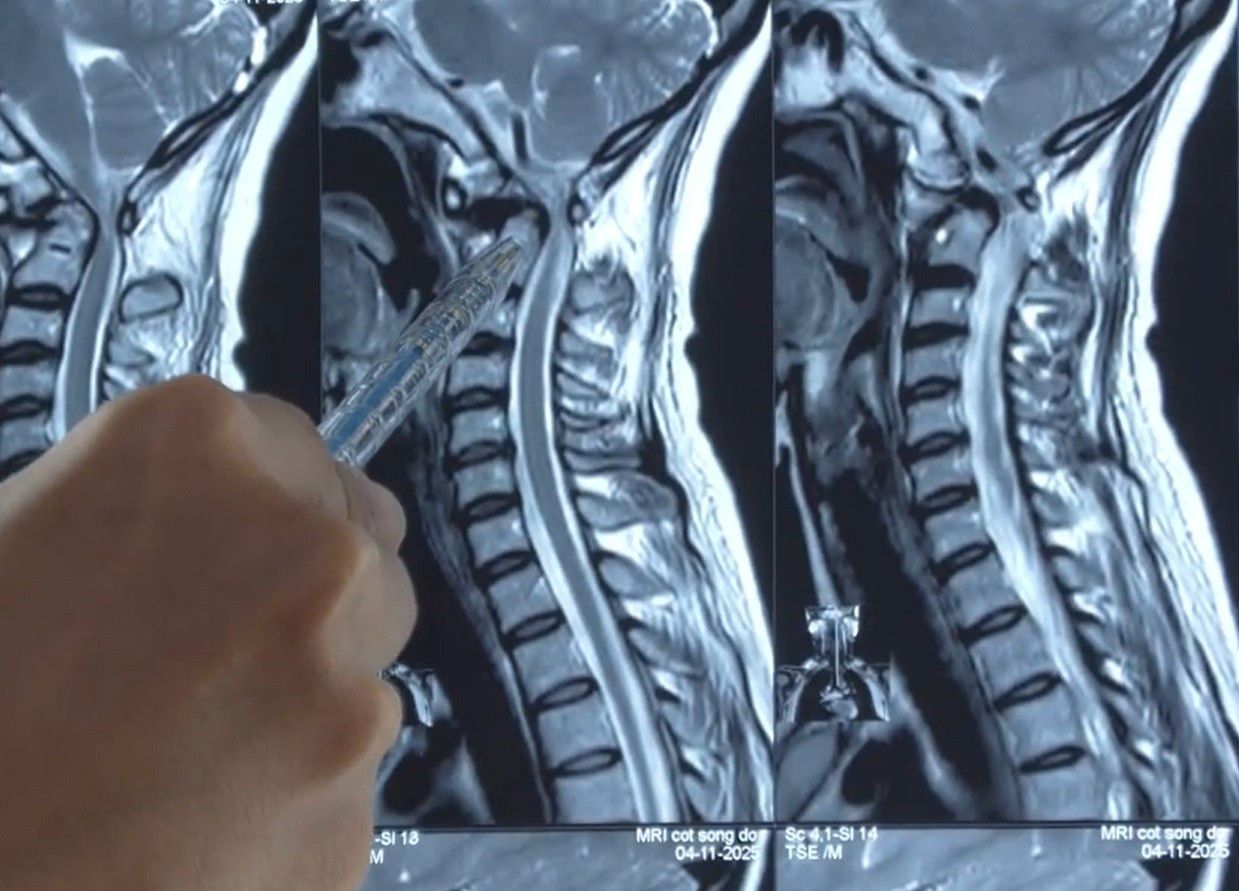

Vị trí đốt sống cổ của người bệnh bị trượt chèn ép tủy sống gây nguy cơ liệt tứ chi

Trong chuyến công tác tại Hàn Quốc, chị bất ngờ ngất giữa sân bay và được đưa đi cấp cứu. Kết quả MRI tại nước bạn cho thấy cột sống cổ bệnh nhân bị trượt tại vị trí C1–C2, gây hẹp nặng ống tủy. Tại đây, bác sĩ khuyến cáo chị phải phẫu thuật càng sớm càng tốt để tránh nguy cơ liệt tứ chi.

Trở về nước, người bệnh đã đến Bệnh viện Đa khoa Xuyên Á TP.HCM điều trị. ThS.BS Trần Vũ Hoàng Dương, Trưởng khoa Sọ não Cột sống 2 của bệnh viện cho biết, bệnh nhân bị trượt đốt sống C1–C2 gây mất vững cột sống cổ và chèn ép tủy nặng. Đây chính là nguyên nhân khiến chị tê dị cảm tứ chi, yếu nửa người bên trái và liên tục ngất xỉu. Chỉ cần một cú ngã nhẹ hoặc xoay cổ sai tư thế, bệnh nhân có thể đối diện nguy cơ liệt tứ chi.

Theo BS Hoàng Dương, cấu trúc bình thường của cột sống cho phép mỏm nha C2 liên kết chặt với thân đốt sống. Nhưng ở bệnh nhân Y. mỏm nha rời khỏi thân, kết hợp với trượt đốt sống đã ép chặt vào tủy cổ – vị trí cực kỳ nguy hiểm. Tình trạng này khiến các dây thần kinh vận động bị đe dọa nghiêm trọng, gây tê yếu tứ chi và suy giảm thị lực.